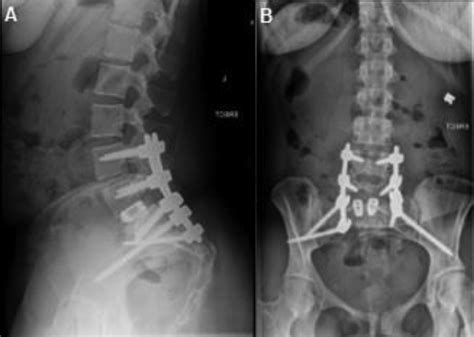

When conservative measures fail to provide adequate relief, or if the patient is experiencing progressive neurological deficits, surgical intervention may be necessary. Sacral Tarlov Cyst Treatment via surgery is complex because the cysts are directly involved with the nerve roots, posing a risk of nerve damage during the procedure. There are several surgical techniques commonly employed:

Microsurgical Decompression An open surgery to remove the cyst wall or reposition it. To permanently decompress the nerve root.

Surgical treatment for Tarlov cysts is not without risk. Potential complications include CSF leaks, which can lead to headaches and require additional procedures, as well as the risk of nerve injury. Furthermore, not all patients experience complete resolution of symptoms, even after a technically successful surgery. Because of these complexities, it is paramount to seek care from a neurosurgeon or orthopedic spine surgeon who has specific, documented experience in treating perineurial cysts.

Patient selection is the most critical factor for success. Surgeons must carefully weigh the potential for improvement against the inherent risks of spinal surgery. A thorough discussion about expectations, potential outcomes, and recovery timelines is necessary before proceeding with any surgical option.